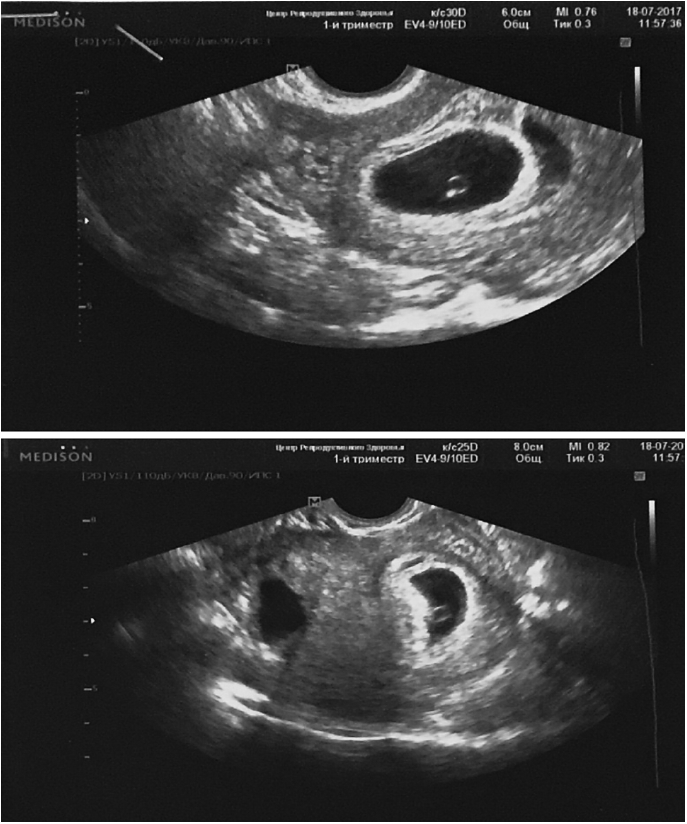

Пациентке проведена программа ЭКО с нативными донорскими ооцитами. Заместительная гормональная терапия в цикле ЭКО с использованием донорских ооцитов у пациентки с яичниковой недостаточностью состояла из трансдермальных эстрогенов 2 мг/сут в течение 12 дней под ультразвуковым контролем за пролиферацией эндометрия. При толщине эндометрия 8 мм и трехслойной структуре к терапии добавлен микронизированный прогестерон 600 мг/сут интравагинально. На 4-й день терапии микронизированным прогестероном в стерильных условиях произведен скретчинг эндометрия по передней стенке внутренней поверхности матки. В месте скретчинга эндометрия появляются повышенное кровоснабжение и гиперкоагуляция. На 5-й день терапии микронизированным прогестероном под контролем УЗИ перенесен эмбрион в полость матки. Через 12 дней после переноса получен рост хорионического гонадотропина. Через 10 дней проведено УЗИ органов малого таза, констатирована клиническая беременность с прикреплением хориона по передней стенке внутренней поверхности матки. В толще миометрия задней стенки матки сохранилась кистозная анэхогенная полость с четким округлым контуром в диаметре 20 мм (рис. 3).

Рис. 3. Беременность при узловой форме аденомиоза.

Fig. 3. Pregnancy in nodular form of adenomyosis.

На фоне гормональной поддержки микронизированным прогестероном 600 мг/сут интравагинально до 20 нед беременности была угроза выкидыша. Со сроком гестации кистозное анэхогенное образование по задней стенке матки уменьшилось и исчезло к 20 нед беременности. Беременность протекала с явлениями хронической фетоплацентарной недостаточности.